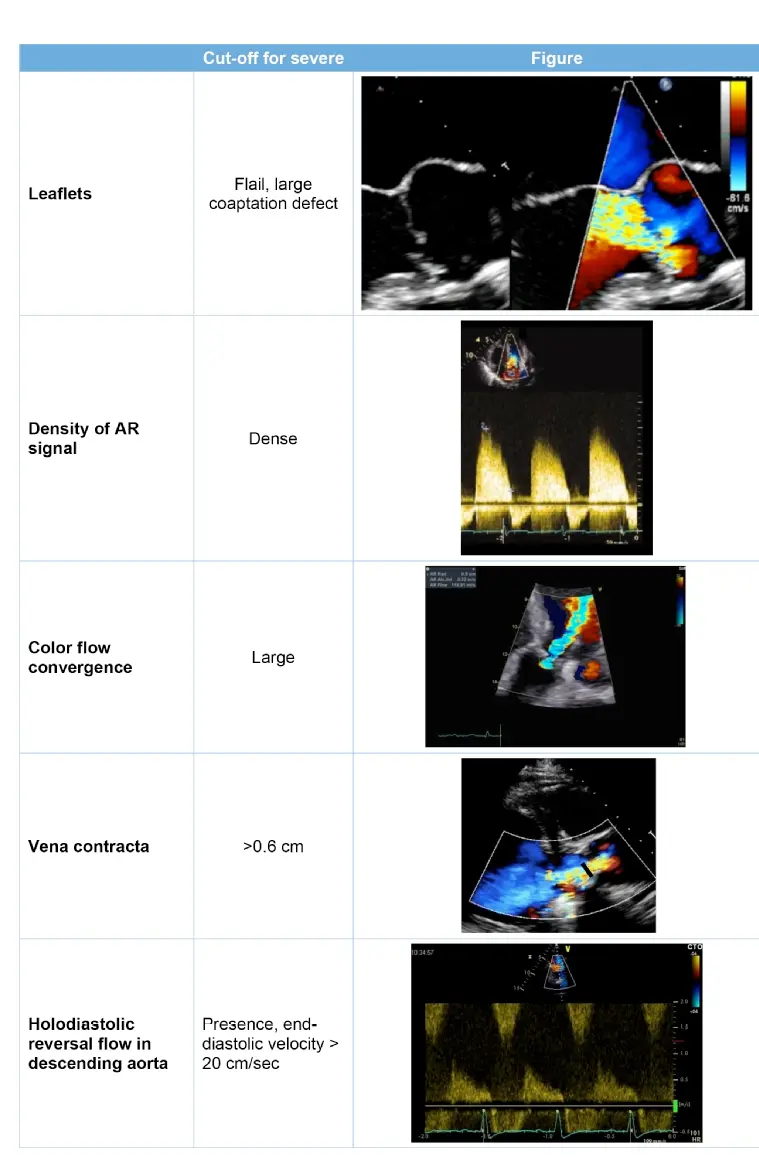

Diagnosis

- Echo

- determine whether there is rapid equilibration of the aortic and LV diastolic pressures; visualizing the aortic root; and evaluating LV size and systolic function

- A pressure half-time of <300 ms on the AR velocity curve indicates rapid equilibration of the aortic and LV diastolic pressures.1

- Quantitative measures of regurgitant volume and EROA are better predictors of clinical outcome1